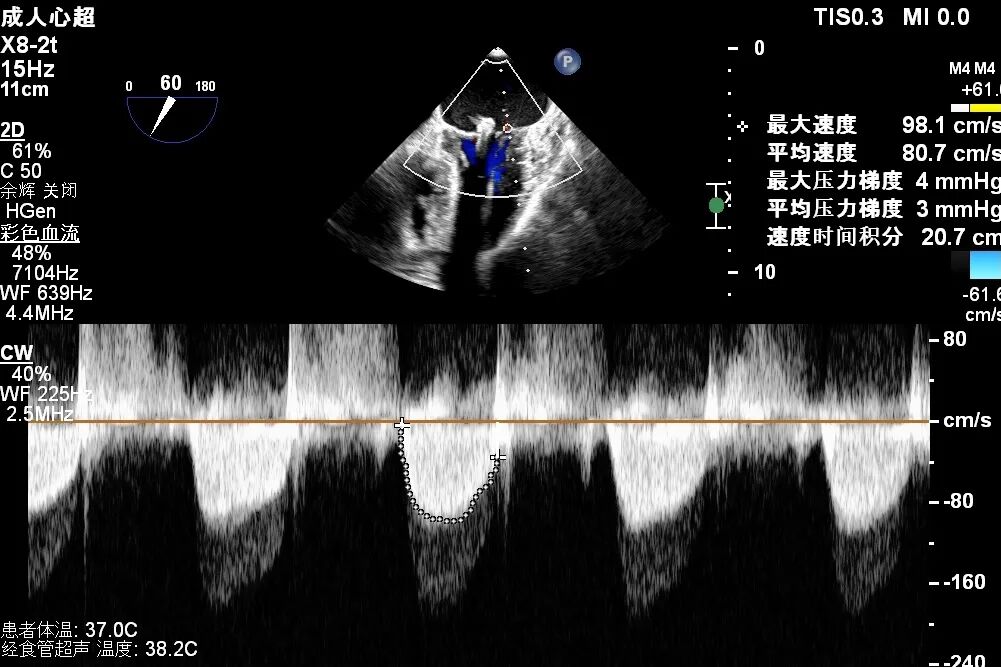

Mitral Valve Repair Stage: Via the transfemoral venous approach, a 4.0 cm atrial septal puncture was performed, and one mitral valve clip was selected. The unique feature of wide-angle deployment effectively resolved the issue of excessive leaflet tension during valve clip closure. Under the precise guidance of ultrasound, one clip was successfully implanted at the site of the widest regurgitation in the A2-P2 segment of the mitral valve. Immediate postoperative TEE assessment showed that mitral regurgitation was reduced to trivial (1+), the mean transvalvular pressure gradient was only 3 mmHg, and pulmonary venous retrograde flow was significantly improved.

Transvalvular Pressure Gradient of 3 mmHg